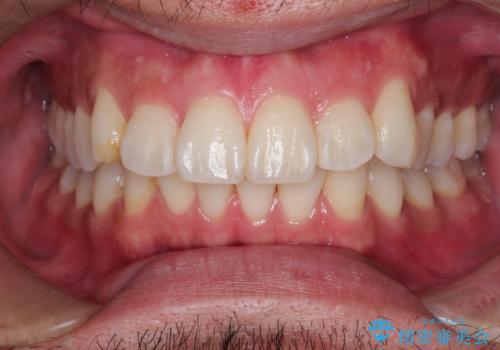

前歯をきれいにしたい オールセラミッククラウンにによる補綴